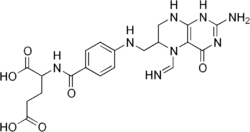

| IUPAC name

(2S)-2-{[4-[(2-Amino-5-methanimidoyl-4-oxo-1,6,7,8-tetrahydropteridin-6-yl)methylamino]benzoyl]amino}pentanedioic acid | |

| C20H24N8O6 | |

| Molar mass | 472.455 |